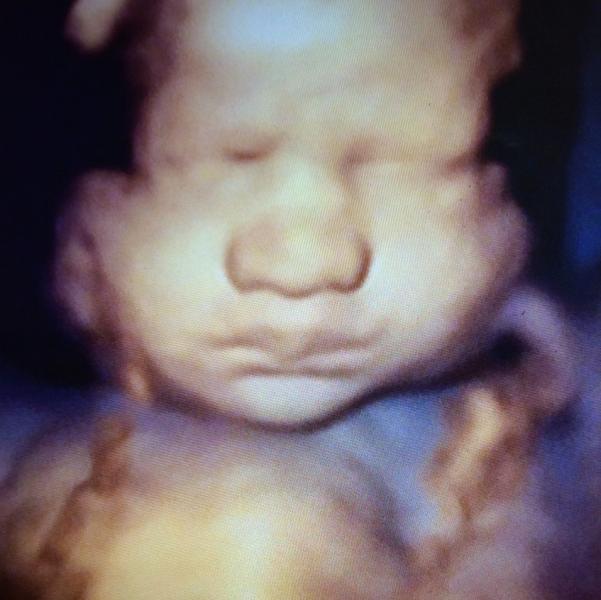

My baby girl